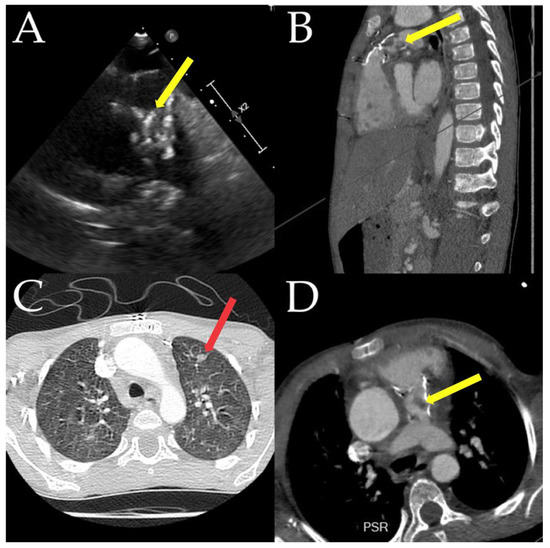

- Chau, A.; Renella, P.; Arrieta, A. Multimodality Cardiovascular Imaging in the Diagnosis and Management of Prosthetic Valve Infective Endocarditis in Children Report of Two Cases and Brief Review of the Literature. Cardiol. Young 2019, 29, 1526–1529. [Google Scholar]

- Parlow, S.; Beamish, P.; Desjardins, I.; Fulop, J.; Maharajh, G.; Castellucci, L. Infected Rastelli Conduit in an Immunocompromised Patient That Was Not Visible on Transthoracic Echocardiogram. CJC Open 2019, 1, 324–326. [Google Scholar] [PubMed]

- Feuchtner, G.M.; Stolzmann, P.; Dichtl, W.; Schertler, T.; Bonatti, J.; Scheffel, H.; Mueller, S.; Plass, A.; Mueller, L.; Bartel, T.; et al. Multislice computed tomography in infective endocarditis: Comparison with transesophageal echocardiography and intraoperative findings. J. Am. Coll. Cardiol. 2009, 53, 436–444. [Google Scholar] [CrossRef] [PubMed]

- Parbhoo, P.; Nell, T.; Meel, R. Assessment of pacemaker lead-related infective endocarditis with three-dimensional echocardiography and cardiac computed tomography. Cardiovasc. J. Afr. 2022, 33, 36–40. [Google Scholar] [CrossRef]